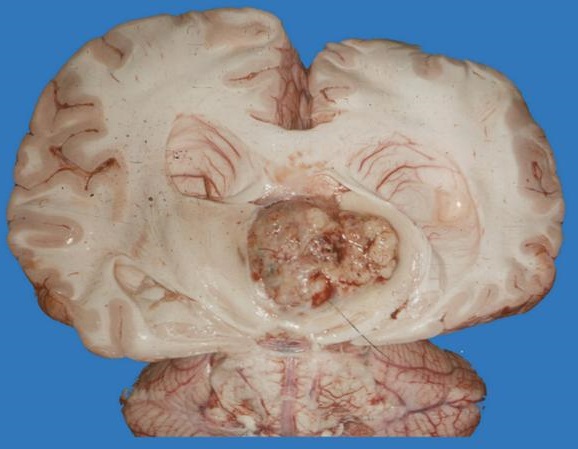

U nguyên bào tuyến tùng (pineoblastoma) là một loại ung thư bắt đầu từ tuyến tùng của não. Tuyến tùng nằm ở trung tâm của não. Tuyến tùng sản xuất một loại hormone gọi là melatonin. Melatonin đóng một vai trò trong chu kỳ ngủ-thức tự nhiên của cơ thể.

U nguyên bào tuyến tùng bắt đầu bằng sự tăng sinh của các tế bào trong tuyến tùng. Các tế bào phát triển nhanh chóng và có thể xâm lấn và phá hủy các mô cơ thể khỏe mạnh.